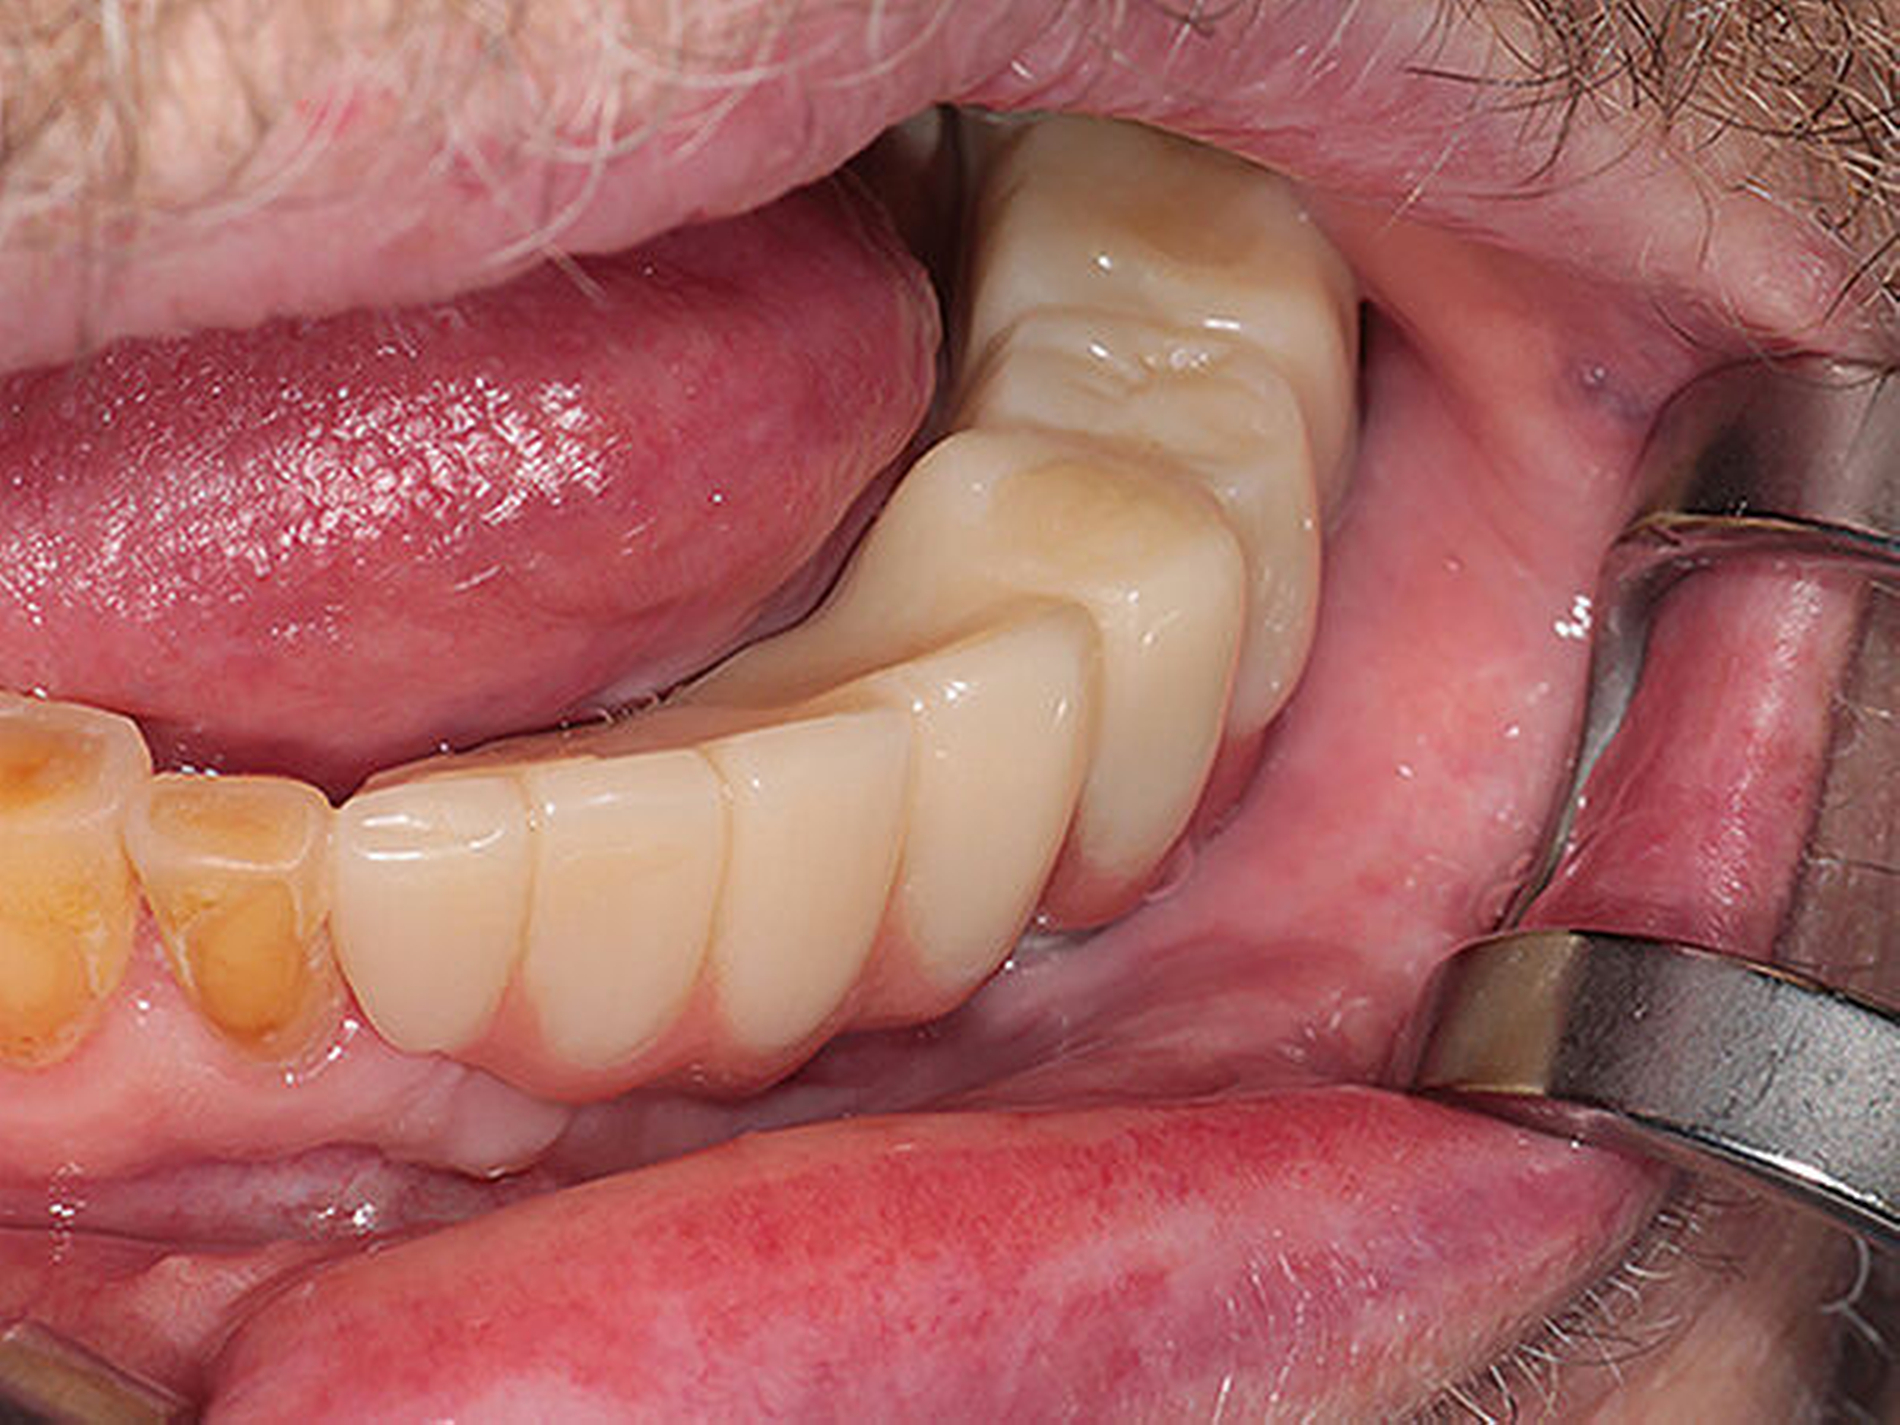

Im nächsten Arbeitsschritt wurde die Brücke intraoral mit korrespondierenden Abutments der jeweiligen Implantate verbunden. Den Abschluss bildete die zahntechnische optische Optimierung (Abbildung 19).

Diese gesamte Konstruktion konnte dem Patienten mit einer hohen Passgenauigkeit eingegliedert werden. Die Abbildung 20 zeigt die annehmbare Farbwahl für ein Langzeitprovisorium in Bezug zur Bezahnung im Oberkiefer.

Abbildungen 20 und 21 zeigen die gesamte Brückenkonstruktion in Bezug zu den Weichgeweben. Der Patient ist mit komplett aufgebauten Stützzonen und einer vollständigen zirkulären Zahnreihe rehabilitiert.